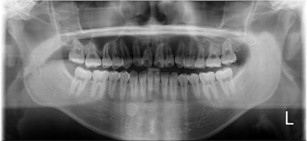

20代 男性

治療前

治療後

治療後- リスク・副作用

- 術後疼痛、歯肉腫脹

- 治療の費用

- 合計¥701,000(税込)

【内訳】

インプラント(1本)¥440,000

その他費用¥261,000

(薬・注射・レントゲン・CT・データ分析・骨造成・サージカルステント・血液検査・仮歯) - 年齢/性別

- 20代/男性

- 患者の具体的な症状

- 1年前に左上12 右上1の根の治療をし、その後放置していたら、左上2が破折した。

左上2インプラント補綴 左上1右上1オールセラミック装着。

歯根破折と虫歯による痛み、審美障害を主訴として来院。 - 検査方法

- コーンビームCT、レントゲン撮影

- 診断結果

- 左上2 歯根破折

- 治療詳細

- 左上抜歯後、インプラント埋入1本

骨造成あり 局所麻酔

インプラント治療後、左上1右上1セラミック修復2本 - 通院回数

- 9回

- 治療期間

- 12か月